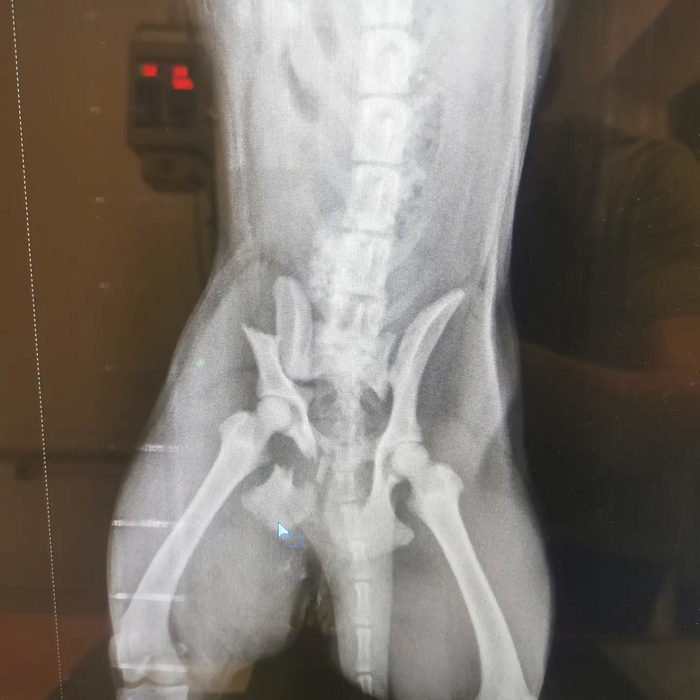

Добрый день! Ребята, нужна помощь. Кто бывает на Обсерваторной, Ростов-на-Дону, возможно видели эту собаку. Она очень ласковая и дружелюбная, возрастом до года. 24.05 мы нашли ее с переломом тазовой кости( скорее всего сбила машина). Отвезли в ветклинику ВотВете на Капустина 16, прогноз у нее хороший, но нужна операция. Такое сокровище нельзя бросать. После операции мы можем забрать ее к себе на восстановление, но не навсегда( у нас уже есть две собаки.

20 тыс за стационар, тесты и рентген + 1 тыс за вызов врача, мы уже отдали ( 15.4 из них собрали жильцы нашего дома, а это уже говорит о контактности собаки), если есть возможность помочь финансово, будем рады (по чекам полностью отчитаюсь). Минимальная стоимость операции 40 тыс. Если кто-то из вас задумывался о заведении собаки, то этот момент пришел) всю информацию о состоянии, плане лечения вы можете узнать у меня или по телефону клиники 88632700101 ( назвали ее Беляш). Собака среднего размера, около 15 кг, подойдет для квартиры( у нас такой же)